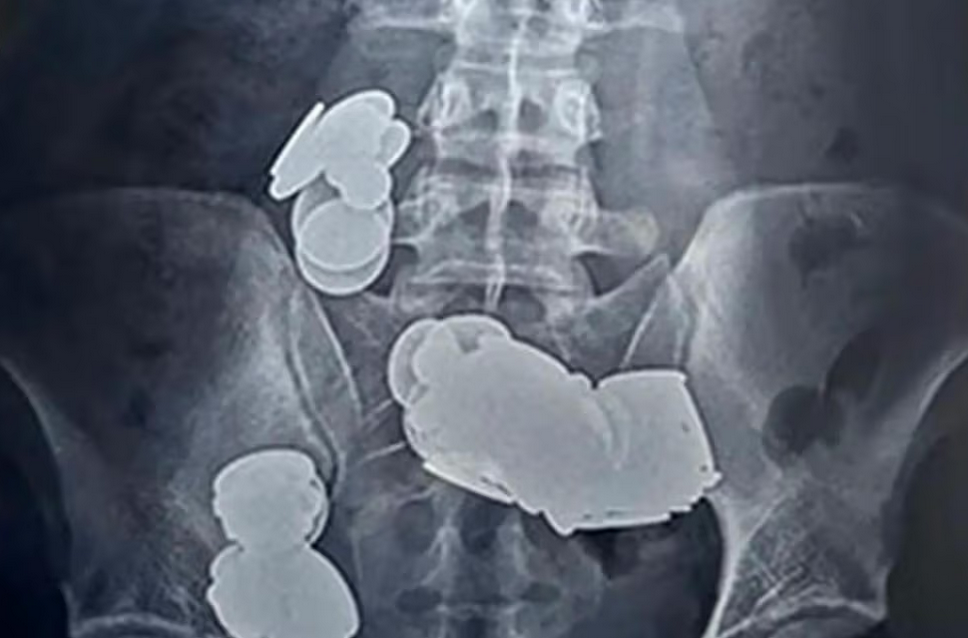

Dvadesetšestogodišnji Indijac vjerovatno je brzo zažalio zbog svoje apsurdne ideje. Kako bi brže došao u top formu, muškarac iz Delhija progutao je 39 novčića i 37 magneta. Ali za svoj čin imao je izuzetno neobičan razlog. Bio je uvjeren da će mu cink u novčićima pomoći u bodibildingu.

Ali posljedice su bile katastrofalne. Mladi Indijac patio je od jakih bolova u trbuhu i nekoliko puta je povraćao. Potražio je pomoć u bolnici, gdje je snimljen rendgenom, izvještava oe24. Ono što su doktori vidjeli na snimcima ih je zapanjilo.

Novčići su se slijepili zbog magnetske sile, što je dovelo do crijevne opstrukcije. Ali 26-godišnjak je imao nevjerovatnu sreću, jer su hirurzi uspjeli ukloniti sve novčiće i magnete, te je pacijent mogao napustiti bolnicu nakon sedmicu dana.